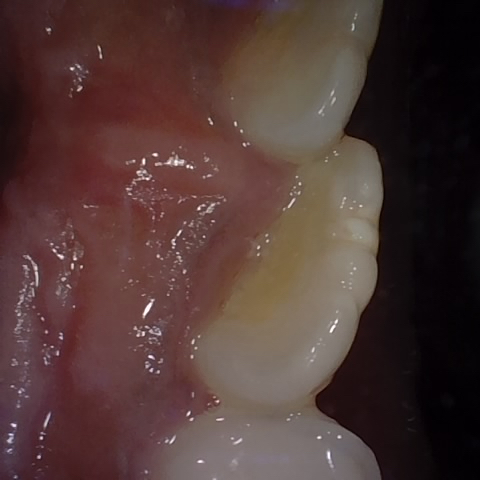

Annotated as "Good"